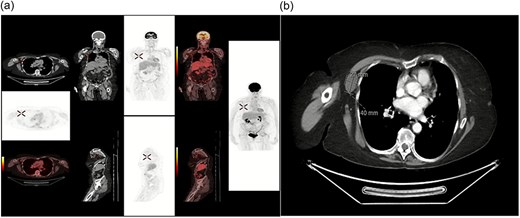

An 83-year-old female independent from home, with a history of multiple resected melanomas and basal cell skin cancers, presented to her general practitioner with a few weeks' history of fatigue, dizziness, and altered bowel motions. Initial CT of the abdomen and pelvis demonstrated a 42 mm lobulated lesion within the mesenteric fat medial to the caecum and terminal ileum, with subsequent colonoscopy revealing two sessile polyps in the rectum and descending colon, which were resected. She proceeded to ileocolic resection, followed by a laparoscopic right hemicolectomy for an incidental bulky mesenteric mass on CT. Interestingly, nodal pathology showed mucinous adenocarcinoma with no clear primary despite a second surgery with full bowel run, as well as a full endoscopy. Other laboratory investigations included full blood count, liver function tests, tumour markers, C-reactive protein, and a computed tomography of her abdomen and pelvis. Time from diagnosis to treatment was 2 years (Fig. 1). Three months later, PET imaging demonstrated an enlarged right axillary lymph node, which was subsequently resected (Fig. 2). Histopathology confirmed mucinous adenocarcinoma.

(a) FDG PET/CT showing hypermetabolic focus in the right axilla, consistent with metastatic disease from a colorectal primary tumour (confirmed with biopsy) (b) CTAP showing incidental right axilla mass.